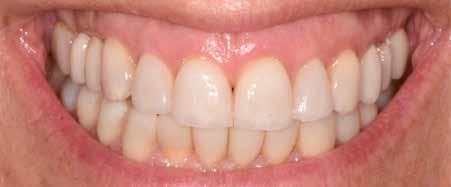

Hölgy páciensem az első konzultáció során tipikus kórtörténetet vázolt fel: Gyermekkora óta szeretett volna fogszabályozó készüléket, hiszen mindig is zavarta a class 2-es eltérésnél tipikusan jellemző nagy overjet (1-3. képek), és természetesen az ezáltal kifelé álló felső metszőfogai, részben a felső metszők protrúziója, részben pedig a disztálisan elhelyezkedő mandibula miatt. Annak ellenére, hogy több fogszabályozó szakorvosnál is járt az évek során, de mivel saggitális eltérése és az alsó metszőfogak torlódása miatt négy kisőrlőfog extrakcióját, illetve emellett sokszor állcsont műtétet is javasoltak neki, nem vágott bele a kezelésbe (4-5. képek).

A konzultáció során arról is beszéltünk – ahogy az ilyenkor lenni szokott –, sohasem szeretett igazán mosolyogni, de a Pitts Protokolloknak köszönhetően az arc- és mosolyesztétikai céloknak megfelelően kerül megvalósításra az okklúziós korrekció. Az okklúziós kezelési célok az alábbiak voltak: a felső és alsó fogív nivellálása és tágítása, az alsó fogsor/ mandibula mezializálása, valamint a harapás megemelése által a mélyharapás rendezése.

A fogkontúrálás és az interproximális redukció alkalmazásával a mikroesztétikai részletek tökéletesítése is megtörtént (11. kép) A kezelés mindössze 16 hónapig tartott, megtörtént a rágófunkció helyreállítása, és az esztétikai végeredmény sokéves várakozás után valóban fordulópontot jelentett páciensünk életében (12-14. képek).